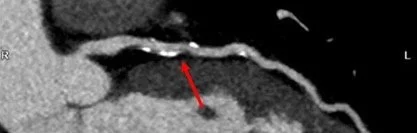

Case Report: Elevated Lp(a) as a cause of severe ASCVD in a healthy veteran athlete with low calculated QRISK3 score

This published case describes one of our clients, a middle-aged former athlete who appeared healthy by every conventional measure, yet whose true cardiovascular risk only became clear through more advanced testing. It embodies the work we do at Andarta: understanding the long arc and medical risks of high performance, and tailoring assessment to the individual rather than the average.